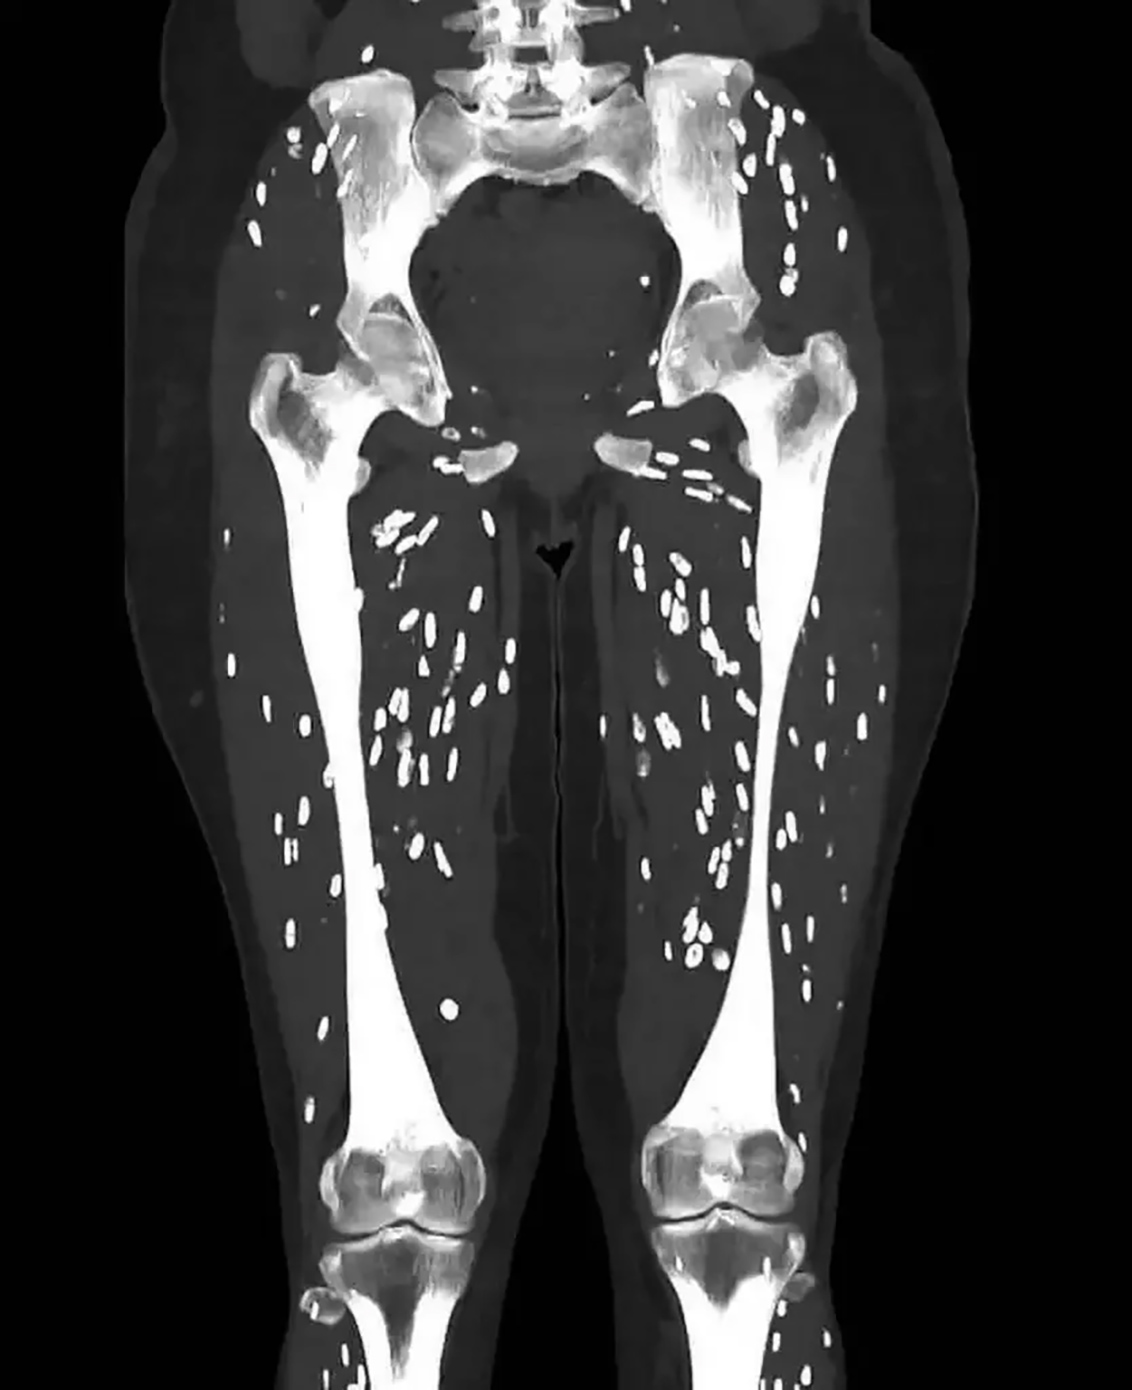

Ο γιατρός Sam Ghali μοιράστηκε στην πλατφόρμα Χ τη συγκεκριμένη εικόνα, μετά την εξέταση σε ασθενή του, ο οποίος έφαγε μισοψημένο χοιρινό. Στην τομογραφία διακρίνονται οι μυς των ποδιών να είναι γεμάτοι με μια παρασιτική μόλυνση, που προέκυψε από το παράσιτο ονόματι «κυστικέρκωση», μια λοίμωξη που προκαλείται από τις προνύμφες του παρασίτου Taenia solium.

Δημοσίευμα της New York Post σημείωσε ότι η «κυστικέρκωση» εμφανίζεται όταν οι προνύμφες του μολύνουν τους ανθρώπινους ιστούς.

«Οι άνθρωποι μολύνονται από το T. solium με την κατάποση κύστεων που εντοπίζονται σε μισοψημένο χοιρινό κρέας. Οι προνύμφες τότε εκκολάπτονται και διαπερνούν το εντερικό τοίχωμα και εισβάλλουν στην κυκλοφορία του αίματος. Εξαπλώνονται ελεύθερα σε όλο το ανθρώπινο σώμα και σχηματίζουν μια σκληρή ασβεστοποιημένη κύστη στους μύες ή στον εγκέφαλο. Οι ασθενείς μπορεί να αισθάνονται σαν να έχουν εξογκώματα κάτω από το δέρμα», ανέφερε ο γιατρός Sam Ghali.